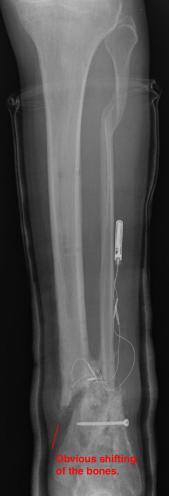

Pre-corrective surgery X-Rays of the damaged right & left legs / ankles

These x-rays were taken at Dr Armendariz’s office, just prior to performing any corrective surgery. As can be seen in these images,

there was no tibia bracing provided by Dr. Keller. Liam was released from Dr Keller’s care with instructions that full weight bearing could

be accomplished within 2 months of Keller’s last surgical procedure. The best example to examine is the second image (from the left) of the

top how. Notice how the bones that should be aligned with the tibia are in fact on the other side of the leg. The third image shows how badly

Liam’s left foot was twisted as a result of the pool placement of the external fixation. What is not obvious is that the screw at the bottom

of the plate on the right fibula missed being screwed into the plate.